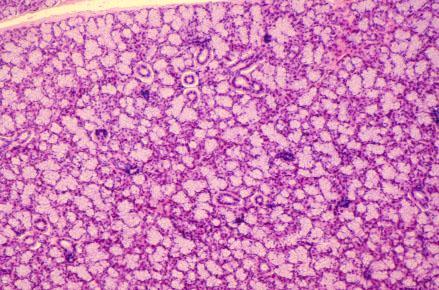

VIII-19, Slide 52, Sublingual Gland (H&E). The sublingual gland is a mixed gland, with clear-staining mucous cells predominating. The ducts scattered throughout the section are intralobular ducts. Intercalated and striated ducts are not present in the sublingual gland.